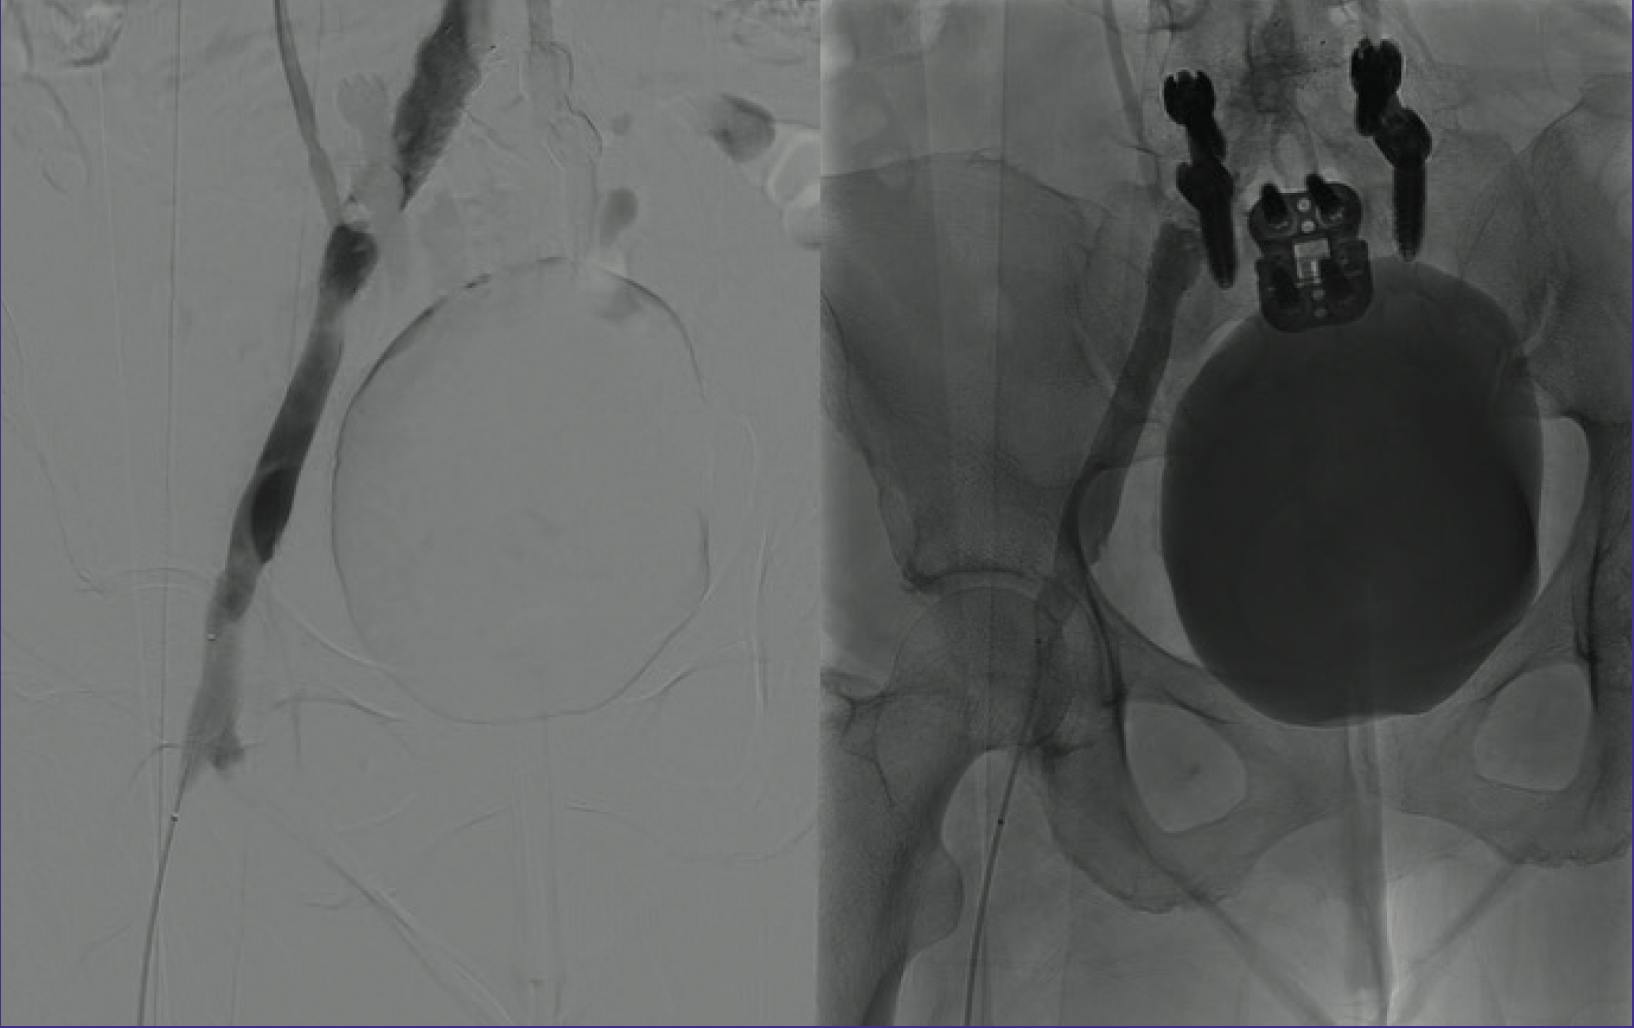

The .035 guidewire was exchanged for a .018 guidewire, and the Pounce™ Venous Thrombectomy System (Surmodics, Inc.) was deployed at the proximal CIV. The system removed acute and chronic thrombus extending from the CIV to the popliteal vein, resulting in restoration of flow (Figure 2). Balloon venoplasty was performed at the May-Thurner stricture in the CIV; however, intravascular ultrasound (IVUS) showed continued stenosis (Figure 3). A 14 X 60 mm Zilver Vena® Venous Self-Expanding Stent (Cook Medical) was deployed at the site of the stricture. Subsequent venography showed occlusive thrombus distal to the new stent (Figure 4). With caution, the Pounce™ Venous System was used to clear the thrombus, and brisk flow was established through the stented CIV (Figure 5).

Figure 4. Thrombus observed distal to newly placed venous stent.